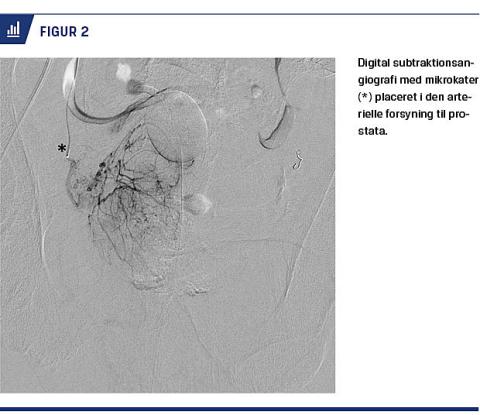

Arteriel adgang etableres ved punktur af arteria femoralis communis og anlæggelse af et indføringshylster, som herefter fungerer som adgangsport for

kateterfremførelse (Seldingers teknik). Ved vanskeligt fremkommelig anatomi kan det være nødvendigt med punktur på begge sider, og alternativt kan en arterie i armen benyttes [19]. Digital subtraktionsangiografi (DSA) er en teknik, som gør det muligt kun at fremstille kontraststoffordelingen, og dermed visualiseres karanatomien i bækkenet. Ved hjælp af kontrastindsprøjtning og DSA styres guidewiren, og begge prostataarterier kateteriseres med et tyndt og fleksibelt kateter (Figur 2). Orientering gøres nemmere ved anlæggelse af et blærekateter med kontrastfyldt ballon, der virker som pejlemærke. Inden der administreres partikler, udføres der en cone-beam-CT (CBCT). Ved en CBCT fremstilles en tredimensional rekonstruktion af anatomien under kontrastindgift, hvilket sikrer korrekt kateterplacering i den arterielle forsyning til prostata uden